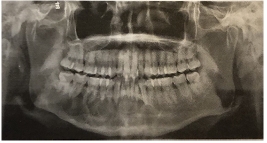

以下圖為例:

上圖曲面體層片顯示下頜骨多囊性、透射性改變,邊界清楚;病變沿頜骨長(zhǎng)軸擴(kuò)展,頜骨無膨?。挥蚁骂M前牙牙根吸收呈斜面狀。